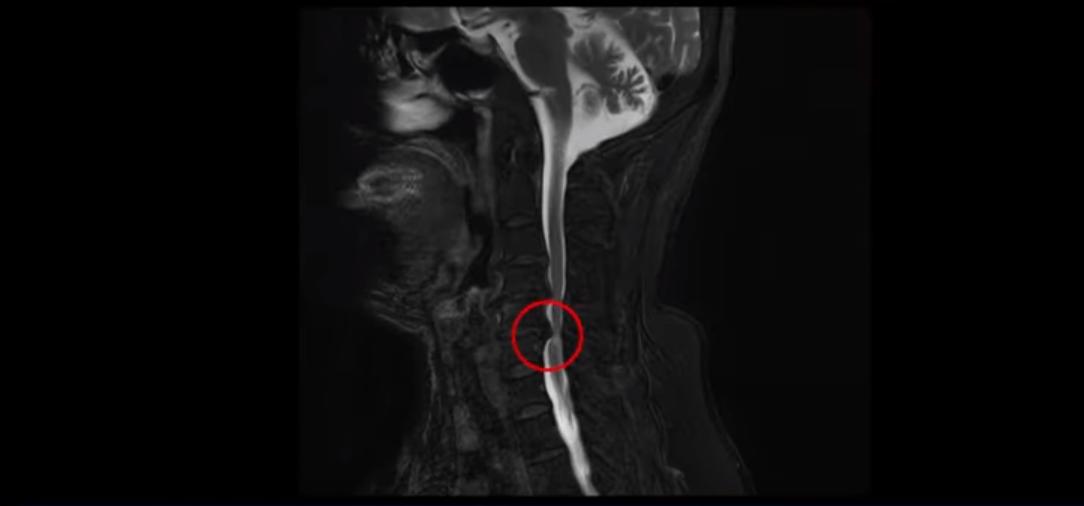

이 환자분은 목디스크 5번, 6번에 심한 디스크로 인해 경추척수증이 발생한 환자입니다. MRI에 보시는 것처럼 디스크가 심하게 밀려나와 이로 인해 척수신경이 눌려 신경손상이 하얗게 보입니다.